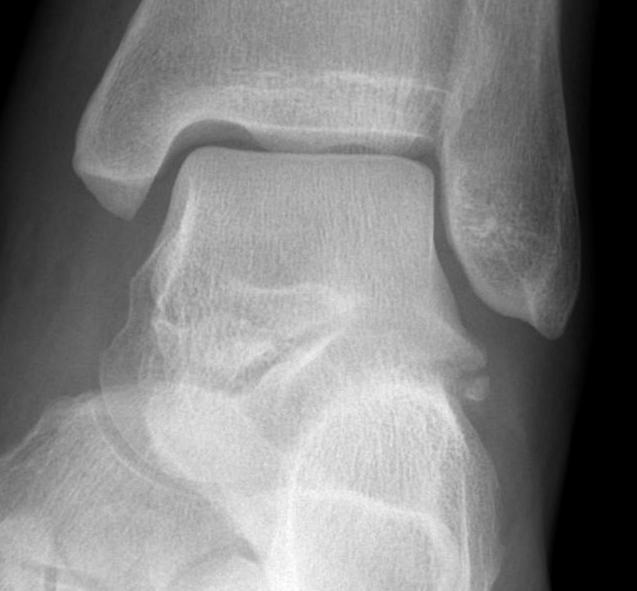

Fracture anterior process of calcaneum